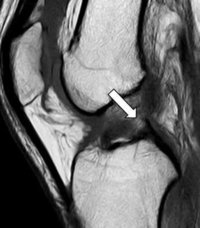

問診、診察に続き画像検査を行います。ACLは単純エックス線写真に写らないため、MRI(磁気共鳴画像装置)検査を行います。MRIでACLの描出が不明瞭ないしは描出されないときは損傷を疑います。またMRIでは、他の靭帯損傷の有無や半月板損傷の有無の確認を行います。